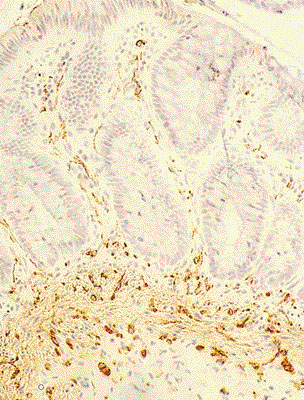

Piesa operatorie - boala Hirschsprung

Irigografie - boala Hirschsprung

Examen histopatologic - boala Hirschsprung